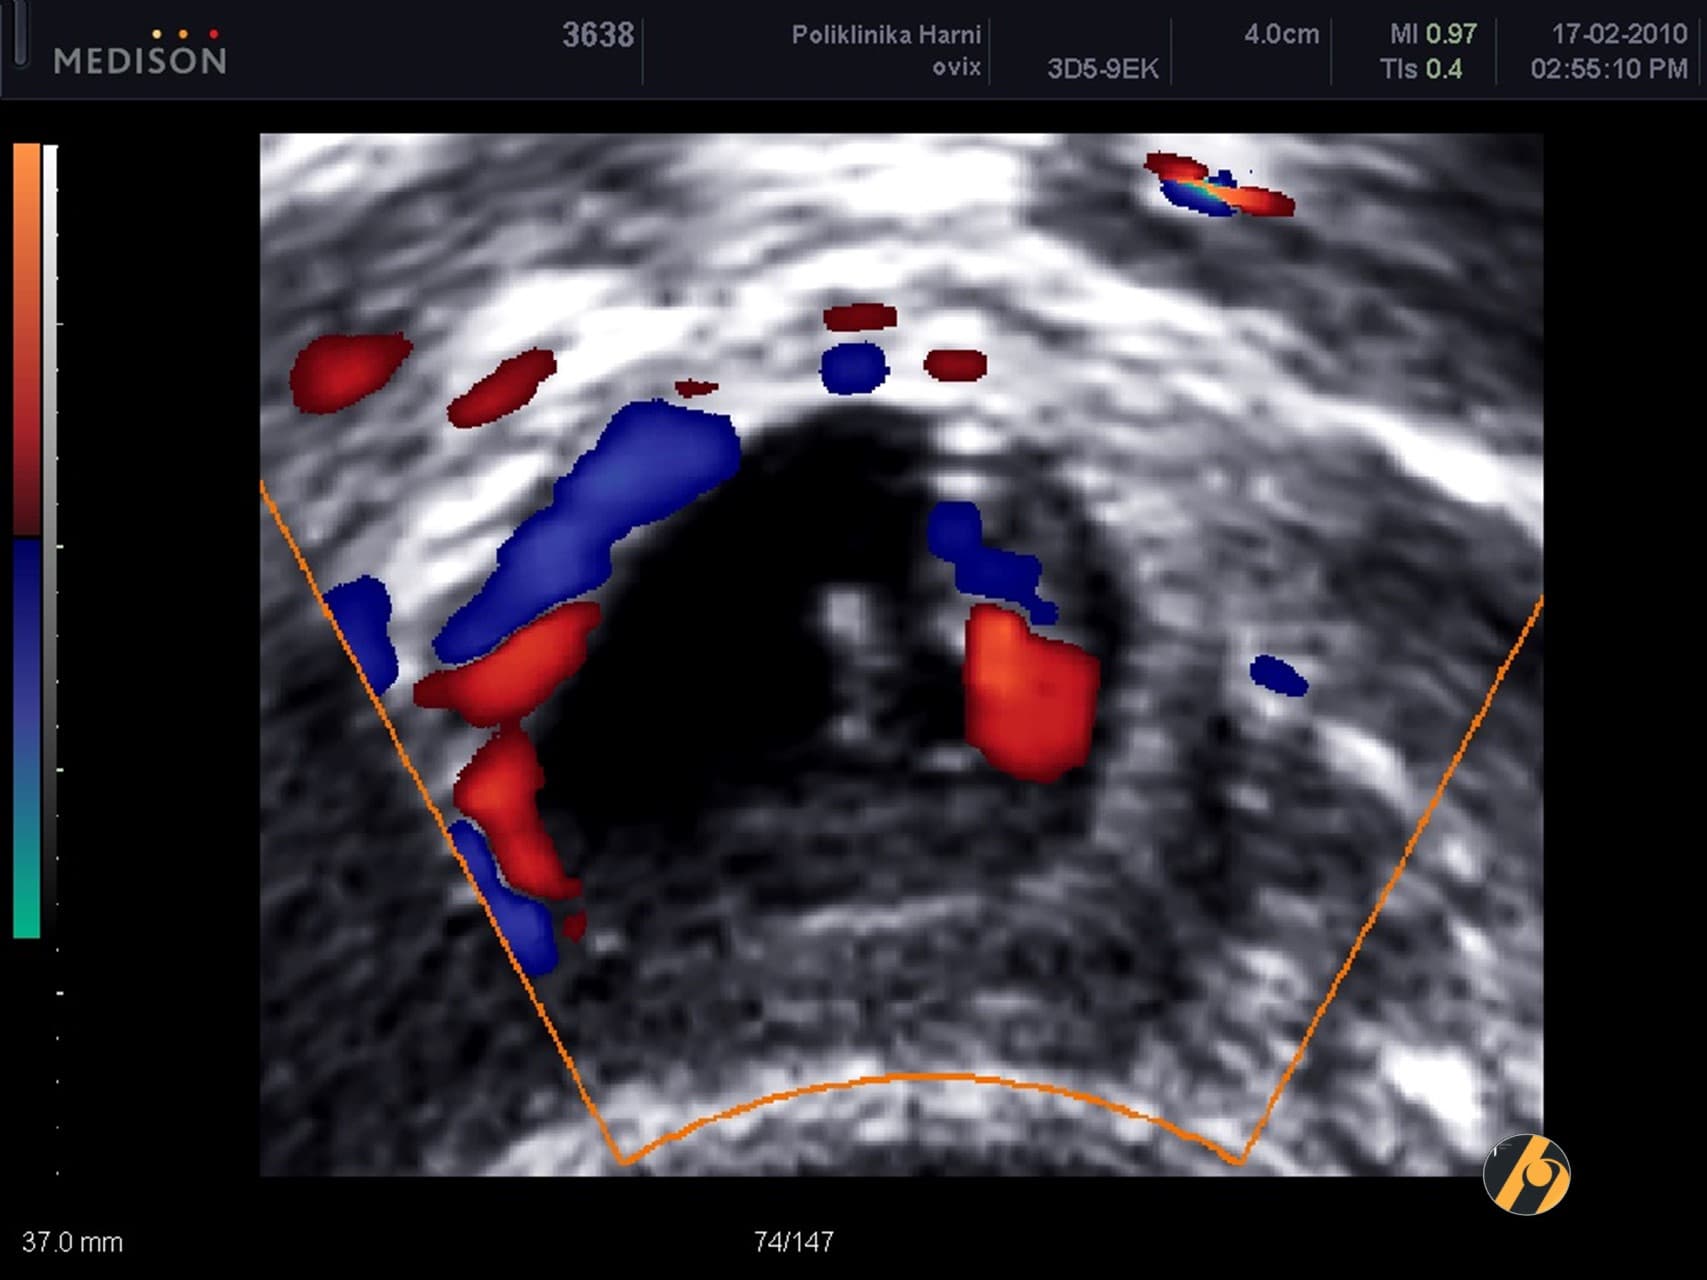

Dvodimenzionalni (2D) UZV nadopunjuje klinički i palpatorni pregled. Njegovu snagu dodatno povećavaju dopplerske tehnologije:

- Kolor Doppler – prikazuje prokrvljenost

- Power Doppler – pojačani prikaz protoka krvi

- Pulsni Doppler – omogućuje merenje otpora protoka krvi

Kolor Doppler je najbolja tehnika u detekciji tumorske neovaskularizacije, jer omogućuje preciznu analizu arhitektonike tumorskih krvnih žila. Malignu neovaskularizaciju karakteriziraju arteriovenski shuntovi, mikroaneurizme, suženja krvnih žila i “slijepa jezerca” krvi unutar tumora. Zahvaljujući toj tehnologiji moguće je preciznije razlikovanje benignih i sumnjivih lezija.

Kombinacija višedimenzionalne ultrazvučne analize s dopplerom postiže vrlo visoku dijagnostičku preciznost, osobito:

- u procjeni malignog potencijala tumora jajnika

- u mapiranju ranog raka jajnika, kada točnost dijagnoze može doseći 97.7–97.8%